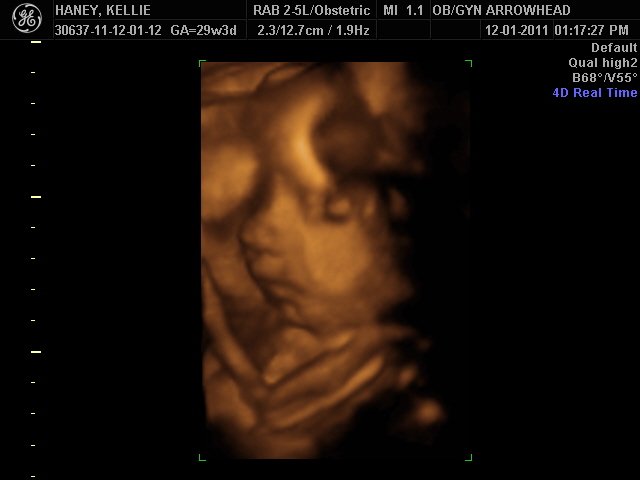

We offer complimentary 3D/4D Ultrasounds to all our OB patients around 30 weeks! The following photos are some examples of our work, shown with permission from our patients.